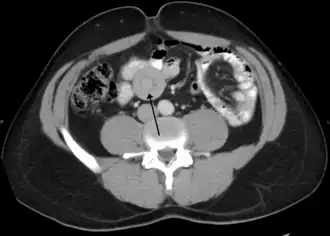

- L’échographie abdominale couplée au Doppler met en évidence le boudin d'invagination : image en cocarde (en coupe transversale) ou en sandwich (en coupe longitudinale). Associée au Doppler couleur, on note une hyperhémie artérielle et veineuse du boudin. Des lacunes hypo-échogènes sont évocatrices d'adénopathies mésentériques. Cet examen a une très bonne valeur prédictive positive[7], ce qui fait qu'il constitue l'examen de première intention en cas de suspicion[8].